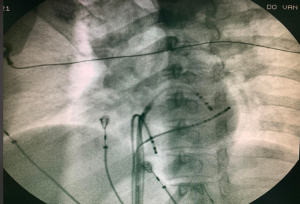

Phương pháp cắt đốt truyền thống được thực hiện dưới màn hình huỳnh quang tăng sáng sử dụng tia X để hướng dẫn đặt các catheter chẩn đoán trong buồng tim và định hình vị trí cắt đốt nhịp nhanh.

Hình nghiêng trái 45° và hình nghiêng phải 30° giúp định hình catheter trong cắt đốt nhịp nhanh kịch phát

Đặt các catheter chẩn đoán dựa trên mô hình 3D và chỉ sử dụng khoảng 1.2 giây tia X cho các bước khảo sát cần thiết.

Tia X (1.2p) được dùng cho thử nghiệm mapping và không liên quan trực tiếp đến bước điều trị.